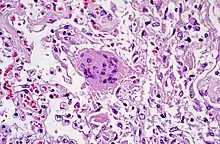

Pathologie du tissu pulmonaire due au SRAS-CoV

Le traitement d’une infection par le SARS-CoV est symptomatique. Une antibiothérapie peut être administrée tant que les causes bactériologiques de pneumonie n’ont pas été éliminées. Une oxygénothérapie doit être envisagée en fonction de la désaturation. La corticothérapie doit être envisagée en fonction du risque de syndrome de détresse respiratoire aiguë (SDRA). La prescription de ribavirine, antiviral utilisé au cours de l’épidémie de 2003, est remise en question en raison des nombreux effets secondaires et de leur gravité potentielle.